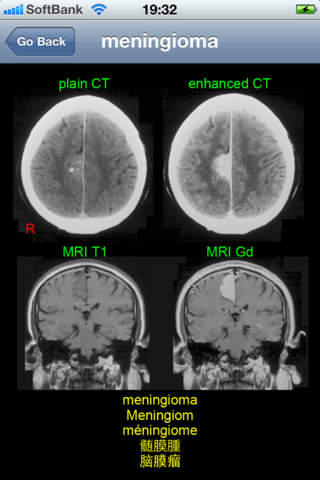

This application is developed to study neuroradiology in English, German, French, Japanese, and Chinese for medical students and professionals such as physicians and nurses. It consists of 26 diagnosis: acoustic neurinoma, acute epidural hematoma, ADEM, aneurysm, arachnoid cyst, arteriovenous malformation, astrocytoma, cerebellar atrophy, cerebral embolism, cerebral hemorrhage, cerebral infarction new and old, cervical disc herniation, chronic subdural hematoma, colon carcinoma metastasis, depressed skull fracture, glioblastoma multiforme, hemorrhagic infarction, meningioma, multiple sclerosis, OPLL, osteoma, pineal cyst, pontine hemorrhage, putaminal hemorrhage, subarachnoid hemorrhage, and syringomyelia.